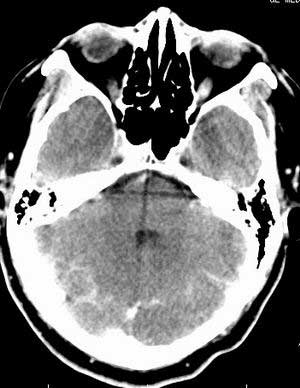

患者男,58岁。耳爆震伤后耳聋2年余,而后双耳道肿胀,间断性流脓。近一月来头痛、恶心、呕吐,右眼红痛,不能入眠。

在平扫时,见右侧枕骨下方小脑半球表面带状模糊稍高密度影,考虑为耳源性脑内感染。